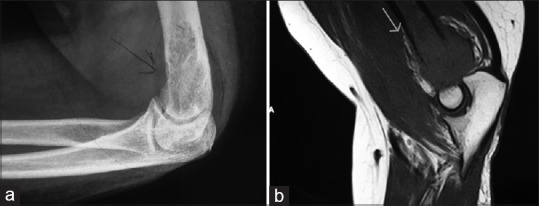

Plain X-ray showed an osteolytic lesion in the distal humerus with soft tissue swelling. The joint space was well preserved. There was no fracture [Figure 1].

| Fig. 1 (a) Plain radiograph and (b) magnetic resonance imaging showing the humeral lesion

Magnetic resonance imaging (MRI) of left elbow showed a lytic expansile lesion in distal metaphyseal region of humerus with cortical erosion. The zone of transition of the lesion with normal bone marrow appears to be wide with irregular margins. There was edema in the muscles around the elbow both anterior and posterior compartments [Figure 1].